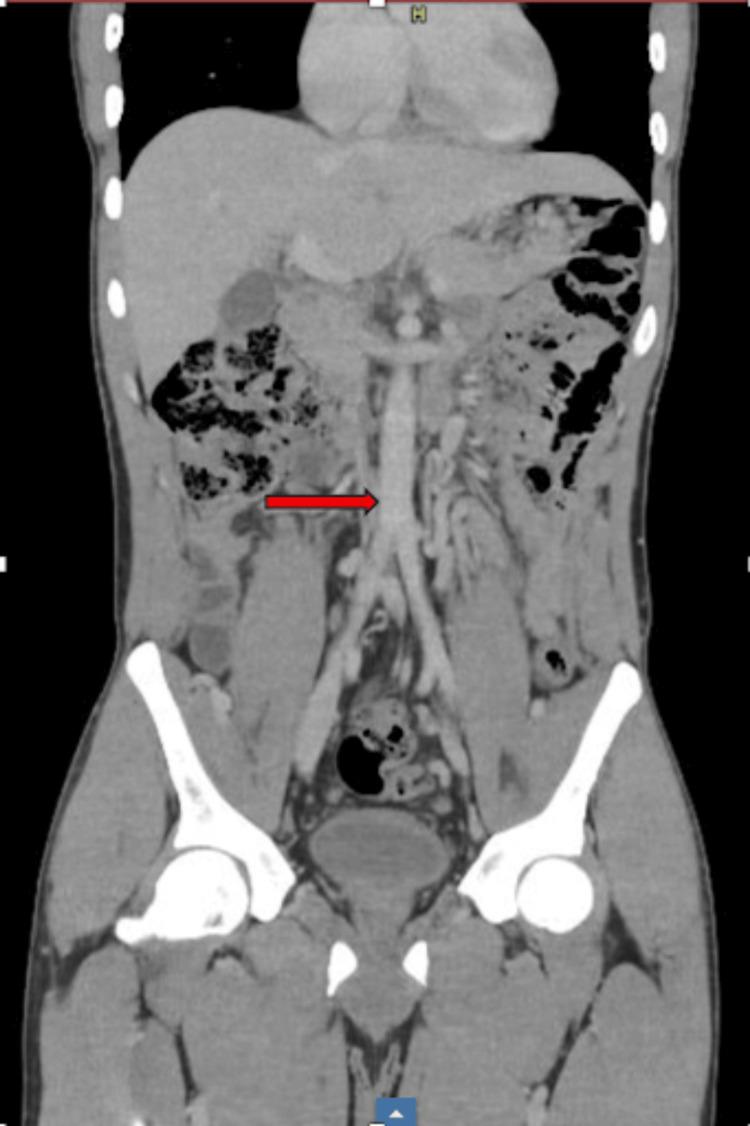

Agenesis of the inferior vena cava (IVC) is a rare congenital anomaly that is frequently identified incidentally in patients presenting with venous thromboembolism. The IVC is susceptible to a wide range of congenital anomalies. Due to its rarity and infrequent clinical encounters, it is often overlooked. We describe the case of a young man of African descent who presented with a deep vein thrombosis due to a previously unrecognized diagnosis of IVC agenesis. This case sheds light on IVC agenesis as an alternative diagnosis, especially in younger patients without traditional risk factors for venous thromboembolism.

下腔静脉缺如是一种罕见的先天性异常,常在静脉血栓栓塞患者中偶然发现。下腔静脉易出现多种先天性异常。由于其罕见性且临床少见,常被忽视。我们描述了一例非洲裔年轻男性病例,该患者因先前未被识别的下腔静脉缺如诊断而出现深静脉血栓形成。该病例揭示了下腔静脉缺如作为一种鉴别诊断的情况,尤其是在没有静脉血栓栓塞传统危险因素的年轻患者中。